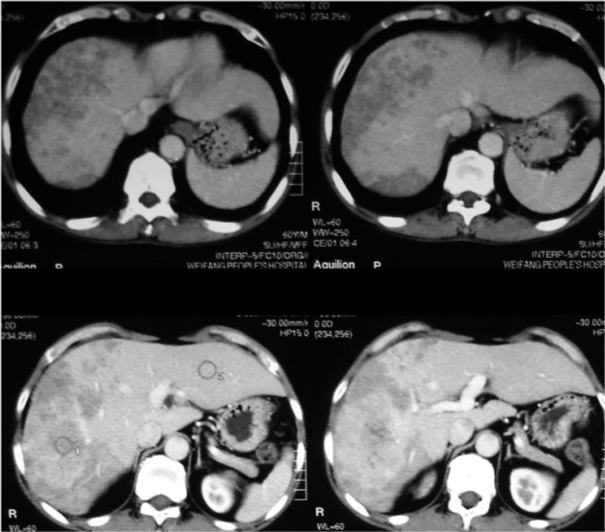

肝硬化ct诊断要点及鉴别诊断

肝细胞肝癌ct病例图片影像诊断分析

乙肝肝硬化伴原发性肝癌deb-tace治疗cr一例

柯丽尔每日一例】酒精性肝硬化合并局限性肝脂肪浸润病变误诊为肝癌